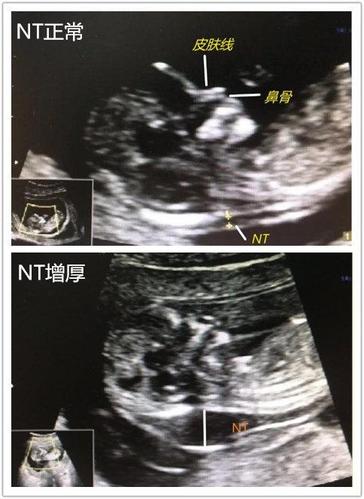

nt标准切面的9幅图,胎儿nt标准测量图片

胎儿基础切面01-nt_超声

超声图像png有hu值孕妈妈要了解孕早期超声筛查之nt

nt筛查标准切面图